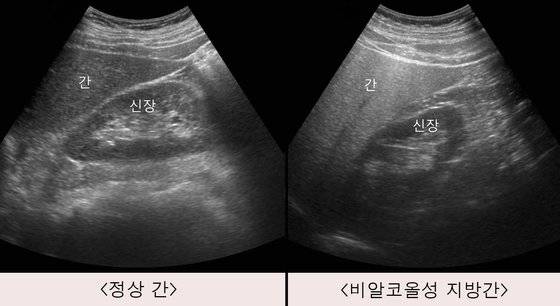

흔히 지방간을 술을 많이 마셔서 생기는 질환이라고 알고 있는 경우가 많은데, 비알코올성 지방간이 지방간의 약 80% 정도를 차지한다. 즉 술을 전혀 안 마시거나 1주일이 소주 1병 이하 정도로 소량씩 마시는 데도 생길 수 있다.

비알코올성 지방간은 대부분 증상이 없다. 증상이 있다고 하더라도 오른쪽 상복부에 답답한 느낌이 들고 약간 불쾌한 느낌이 드는 정도다. 하지만 우리나라 성인의 약 3~4명 중 1명은 비알코올성 지방간이라고 할 수 있을 정도로 매우 흔하다.